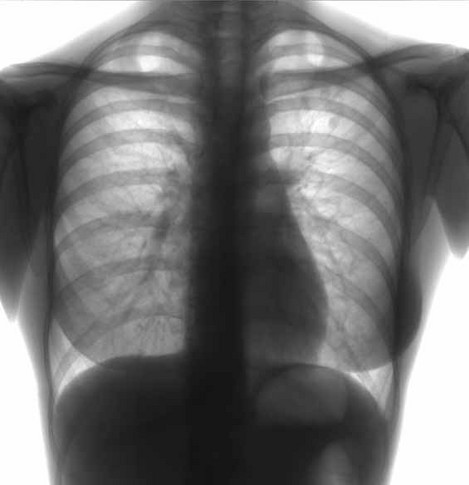

Флюорография – это первый и один из самых главных методов выявления туберкулеза даже на стадии, когда симптомы не очень явные и заболевший их не замечает.

Для начала нужно пройти флюорографию. Это нужно делать хотя бы раз в год, даже если нет никаких подозрений на туберкулез. В Украине эта процедура бесплатная. Приходишь к участковому терапевту и берешь направление на флюорографию. Кстати, талончик-направление на такое исследование обязаны бесплатно выдать, даже если вы обратились в поликлинике не по месту прописки!

Если на снимке доктор увидел затемнения, он направляет пациента на рентгенографию органов грудной клетки и на бактериологическое исследование мокроты. Что и как – решает уже ваш лечащий врач.